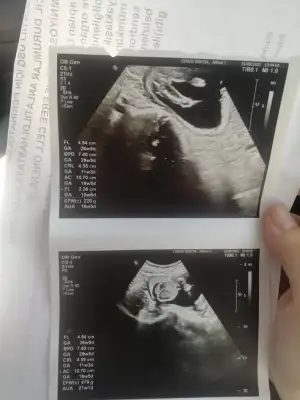

Eklentiler

• IMG_20220816_135723.webp

IMG_20220816_135723.webp

32,7 KB · Görüntüleme: 87

kızlar bugün kontrolden çıktım, magnezyumum bitmişti kasılmalarım olmaya başlamıştı yine doktor hep devam edeceksin dedi. 19. haftadayım bebeğin eşi de yukarı da çıkmaya başlamış çok şükür, 300 gr 20 cm olmuş doktor çok hareketli bebek dedi :nazar: 2 hafta sonra detaylıya gireceğim inşallah.